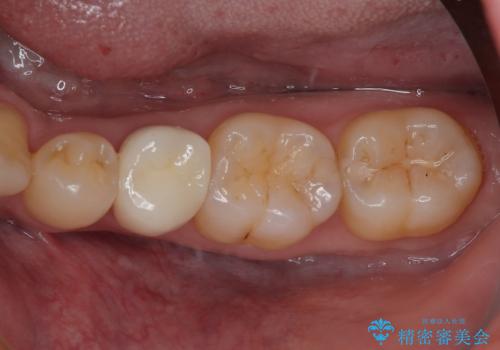

歯が割れた オールセラミッククラウン

- 歯が割れたことを主訴に来院された患者様です。割れた原因としては噛み合う歯が強化セラミックスのみでできたフルジルコニアクラウンであったことと、大きな詰め物が入っていて自分自身の歯の範囲が少なかったことが考えられます。応急で来院されたときには暫間的に強力な接着剤で固定しました。

CT を撮影して確認したところ、歯肉より4ミリ程度深い場所で破折していました。患者様と相談して、外科的な介入はせずに被せもののみでの治療を行うこととしました。

拡大鏡視野下で詰め物と虫歯の除去を行い、詰め物の範囲が大きかったためオールセラミッククラウンに適した形に整えました。

型どりはシリコーン印象材にて精密印象をしています。

痛みもなく、適合もよく、機能的に問題もなく、見た目も満足されていました。

嚙む力(咬合力)がとても強い方なのでナイトガードを今後使っていただく予定です。